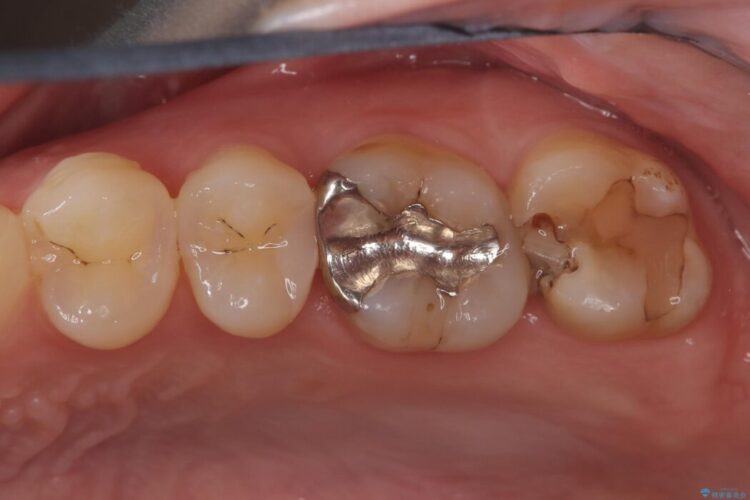

詰め物内部の虫歯治療、隠れた根管の発見

詰め物内部の虫歯治療、隠れた根管の発見 ビフォー 詰め物内部の虫歯治療、隠れた根管の発見 アフター

奥歯の詰め物が取れたとご来院された患者様です。